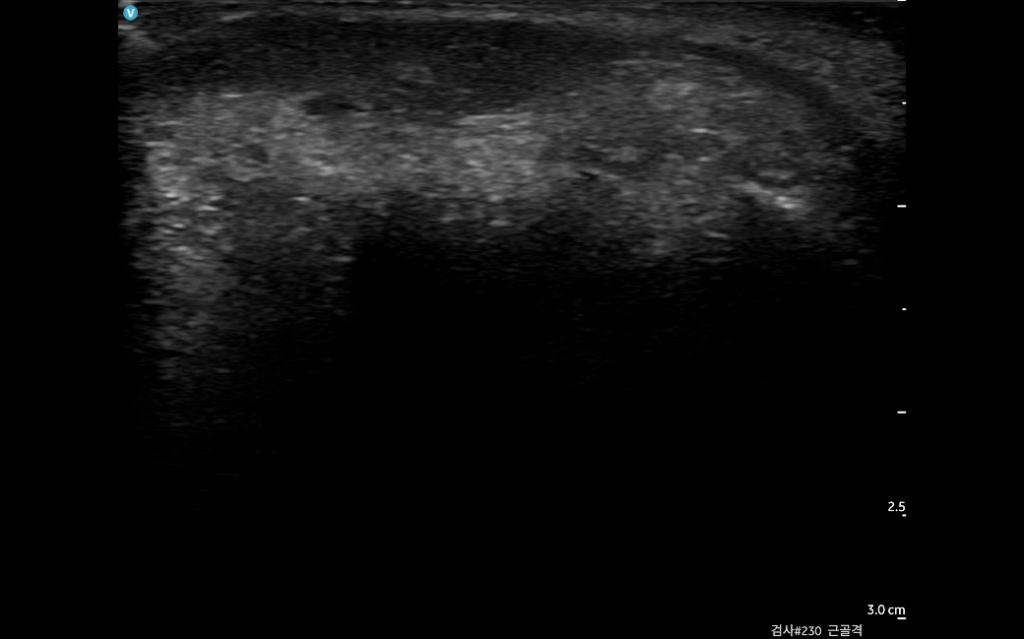

눈밑지방재배치했는데 한쪽만 불룩하게 멍울이 생겼어여 ㅜ 붓기라고 기다리라했는데 도저히 사람몰골이 아니라 초음파를 봤거든여

여기병원 원장님은 지방이나 필러론 안보이고

염증덩어리로 보인다는데 다른 원장님들 의견이 궁금합니다 ㅜ

• 2번 째 사진

첨부하신 초음파사진만으로는 알기가어렵습니다 해당병원 원장님과 상의하시는게 맞습니다.